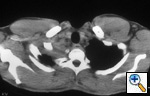

Fig.

11: Computed tomographic

scan of the chest showing

superior sulcus tumor in

the right apex with no

evidence of vertebral body

invasion, T3. |